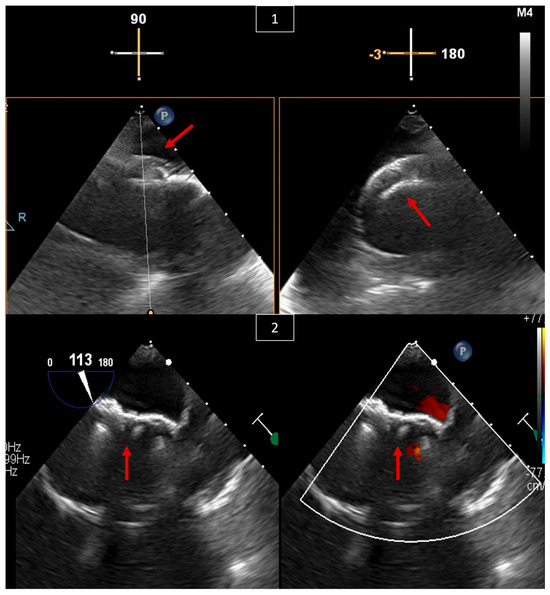

5. Paravalvular Leak Intervention